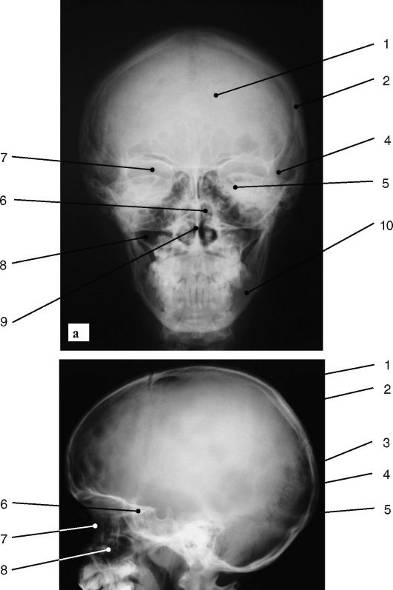

Обзорные рентгенограммы черепа в прямой и боковой проекциях являются основой для изучения костей мозгового и лицевого черепа (рис. 3)

Рис. 4. Обзорные рентгенограммы черепа (а - прямая, б - боковая проекции): 1 - лобная кость; 2 - теменная кость; 3 - затылочная кость; 4 - височная кость; 5 - клиновидная кость, 6 - решетчатая кость; 7 - глазница; 8 - верхняя челюсть и верхнечелюстная пазуха; 9 - носовая перегородка; 10 - нижняя челюсть